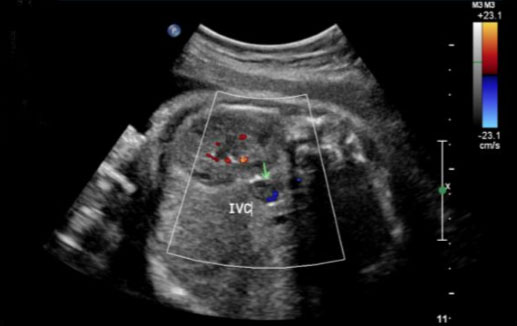

During this pregnancy, our patient was on 40 mg subcutaneous low molecular weight heparin (LMWH) daily for VTE prophylaxis due to her history of DVT and low-risk thrombophilia as well as 81 mg aspirin daily. Her first and second trimesters were uncomplicated. The patient began antenatal testing at 32 weeks of gestation, consisting of fetal heart rate monitoring and ultrasounds. Weekly biophysical profiles (BPP) were reassuring. At 32 weeks of gestation, growth ultrasound was normal, showing an estimated fetal weight of 2688 g. At 34 weeks and 3 days of gestation, her BPP was normal; however, the ultrasound showed a finding concerning for a fetal thrombosis in the IVC (Figure 1, Figure 2, Figure 3).

Figure 1: Prenatal ultrasound of fetus in sagittal plane with Doppler color flow surrounding inferior vena cava thrombosis.